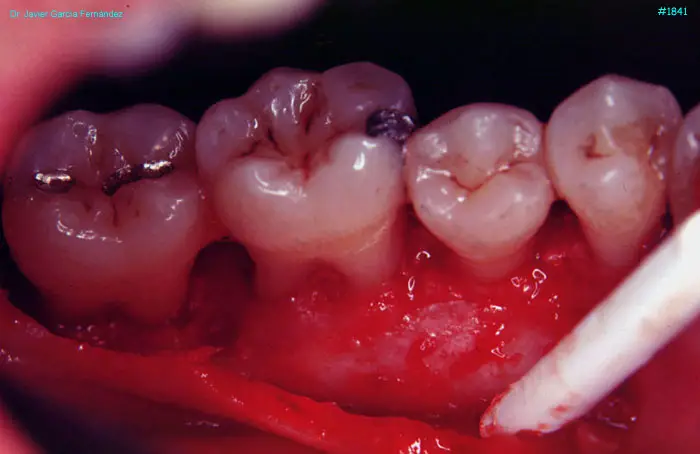

image 107